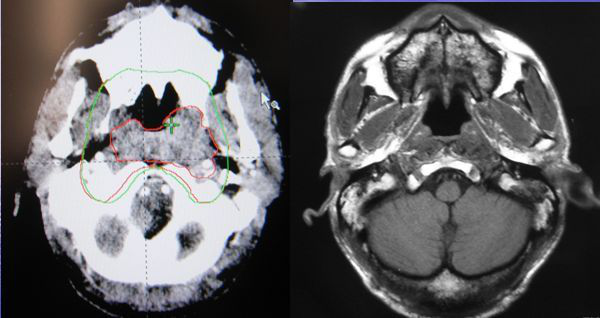

不同的放疗技术对鼻咽癌的治疗效果也不一样。鼻咽癌最好的放射治疗技术是调强放射治疗(IMRT)。胡群峰教授表示,国际肿瘤医疗中心引进的瓦里安TrueBeam直线加速器拥有的调强放疗技术是从5个以上方向照射肿瘤,提高治疗效果的同时减少正常组织损伤。